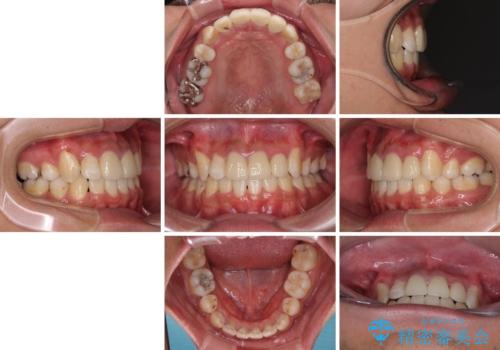

デコボコと変色した前歯 抜歯矯正と審美歯科治療

- 八重歯と上顎前歯の変色を気にして来院された患者様です。

上下ともに八重歯が顕著であったため、上下左右の第一小臼歯4本を抜歯し、ワイヤー装置での抜歯矯正を行うこととしました。

前歯は根管治療が必要な歯を事前に根管治療を行い、矯正治療後にオールセラミッククラウンにて補綴治療を行うこととしました。

前歯の歯列が整ったことで、歯磨きが大変やりやすくなり、患者様には大変満足していただけました。